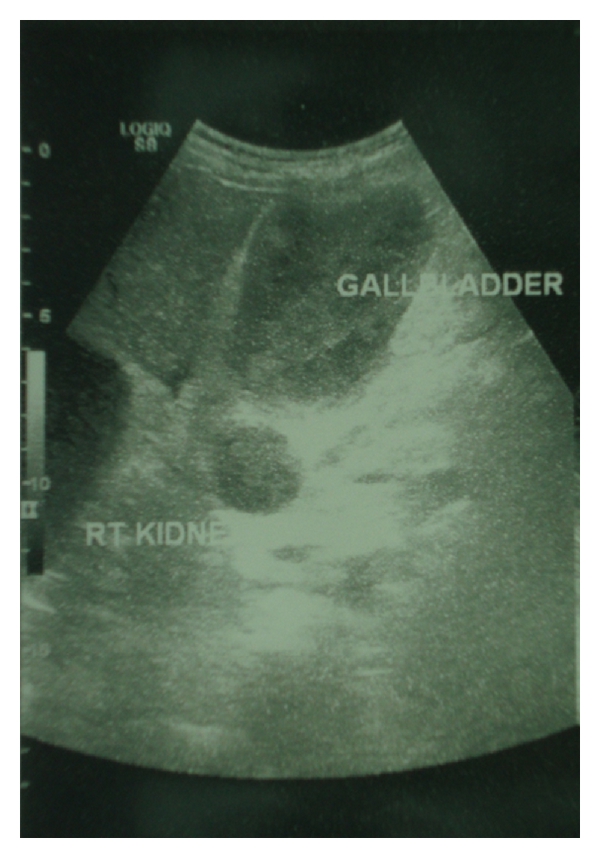

A 70-year-old male with end-stage renal failure was referred to our surgical department owing to abdominal pain localized in the right upper quadrant, 2 hours after hemodialysis. The patient suffered from CRF secondary to mesangioproliferative glomerulonephritis and commenced short dialysis sessions using routinely enoxaparin (40 mg) via the arterial port 3 to 4 minutes prior dialysis, as anticoagulation. Direct questioning revealed no other past medical history and no use of oral anticoagulants or antiplatelet medications. Physical examination revealed localized tenderness and palpable mass in the right upper quadrant. The patient was hemodynamically stable. Axillary temperature was 36.6°C. Initial laboratory and coagulation tests were normal. An ultrasound scan demonstrated a distended GB containing echogenic bile without stones in the lumen and no enlargement of the biliary (intra- and extrahepatic) ducts or hepatic or pancreatic focal lesions (Figure 1). The exact nature of this material was thought to represent thick sludge, pus, or blood.